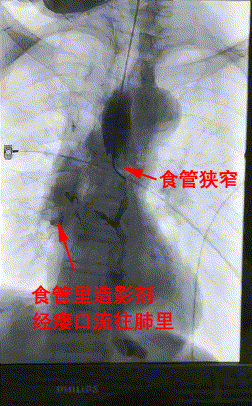

△術前DSA造影顯示:食管狹窄+食管氣管瘘。

楊阿姨是一名罹患食道癌有5年的患者,近半個月來一進食就嗆咳、嘔吐,滴水難進,而原因就是“食管狹窄+食管氣管瘘”。食管狹窄導緻連喝水都難以進胃,因食管與氣管之間的瘘口,水還流進了肺裏。患者異常消瘦,若不積極治療理論上壽命不超過1個月。

3月28日上午,楊阿姨被送進了介入手術室,李旭丹主任等專家根據術前方案上台施術,先采用飛利浦DSA開展食道造影,明确食道狹窄端及瘘口位置,後經導絲引入食管支架釋放于準确位置。DSA顯示支架成功擴張食管狹窄端并封閉瘘口,順利完成手術。